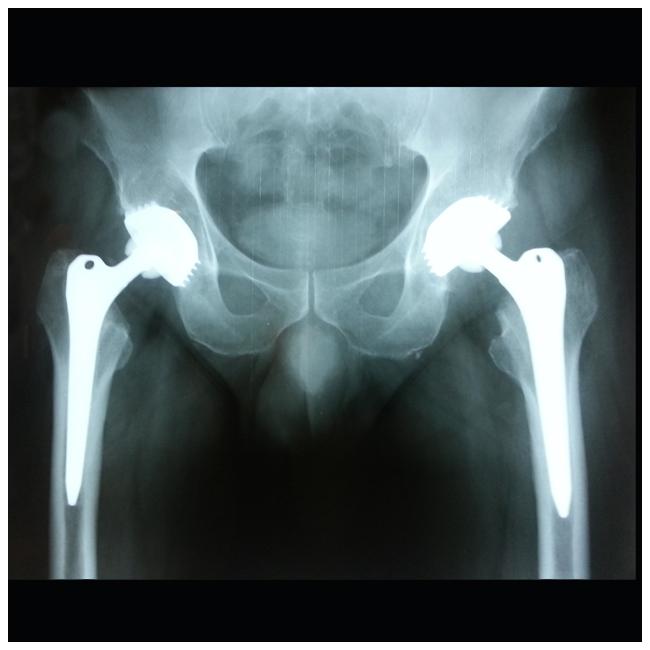

Αρθοπλαστικές Χαλάνδρι, Επανορθωτική χειρουργική Χαλάνδρι